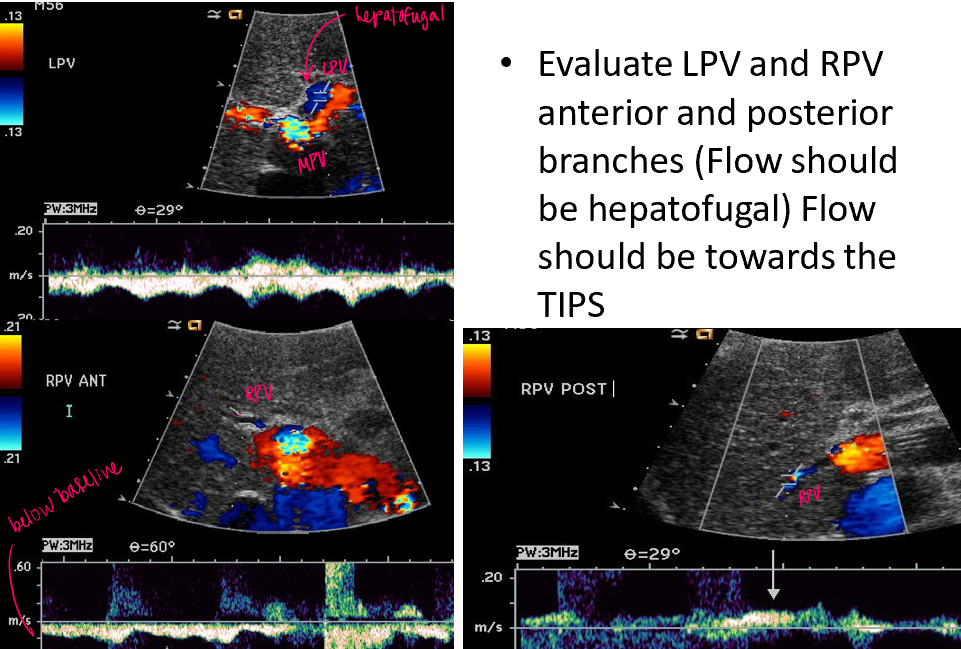

how does flow direction change in the MPV, LPV, RPV, Hep Art, with TIPS stent?

all vessels exhibit hepatofugal flow except the MPV (hepatopedal or bidirectional)

how do we know if TIPS is functioning properly?

velocities in TIPS between 70-200 (or 90-190) cm/sec

LPV flow reversed (hepatofugal)

RPV flow reversed (hepatofugal in anterior and posterior branches)

MPV proximal to TIPS velocity → >30cm/s

Qs A proper functional TIPS would demonstrate what kind of flow in each vessel?

LPV : hepatofugal

RPV (ant) : hepatofugal

RPV (post) : hepatofugal

MPV : hepatopetal / bidirectional